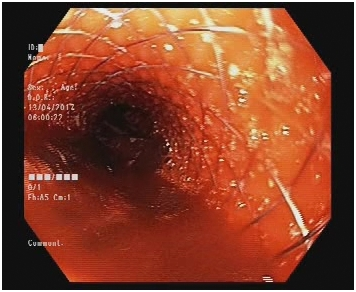

Antimicrobials were escalated empirically. Upper GI endoscopy revealed diffuse mucosal oozing from the lower end of esophagus along with small isolated gastric varix. Glue injection was done, however patient continued to bleed despite supportive measures. Repeat UGI scopy was done, which showed continued generalized ooze from lower end of esophagus. Therefore endoscopic guided Ella danis SEMS was placed with upper end at 25 cm from GE junction. The patient was stabilized and moved to the intensive care unit. There was no subsequent evidence of upper GI bleed. Patient however continued to deteriorate due to pulmonary sepsis. He later succumbed and expired on POD 22 (Figure 1) (Figure 2).

Figure 1 Endoscopic view of Dannis Ella stent in situ.